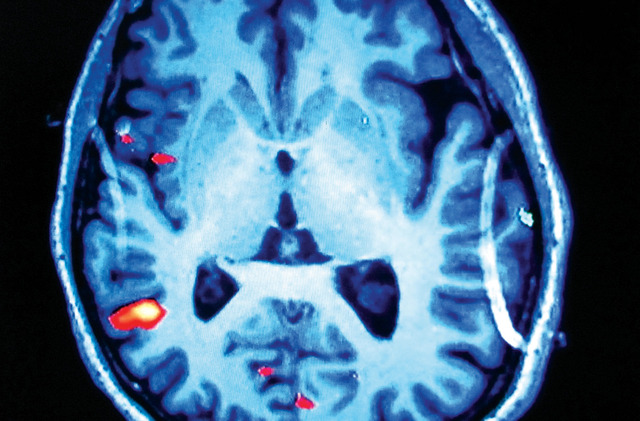

تمكن باحثون في كلية الطب بجامعة ستانفورد ومستشفى لوسيل باكارد للأطفال بالولايات المتحدة من تحديد عدة طفرات جينية مسؤولة عن الورم الدماغي الأكثر انتشارا بين الأطفال، والذي يدعى الورم الأرومي النخاعي، مضيفين بذلك أدلة إلى النظرية القائلة بأن التشخيص عبارة عن مجموعة من الأمراض السرطانية المميزة وراثيا مع تكهنات مختلفة.

وقال الباحثون إنه يرجح لهذه النتائج أن تؤدي إلى أساليب علاجية أقل سمية وأفضل استهدافا على مدى العامين المقبلين. وقال احد الباحثين : ( إننا نميل الى معاملة جميع الأورام الأرومية النخاعية على أنها مرض واحد . وتمثل الدراسة نظرة أكثر دقة للمشهد الجيني لهذه الأورام .